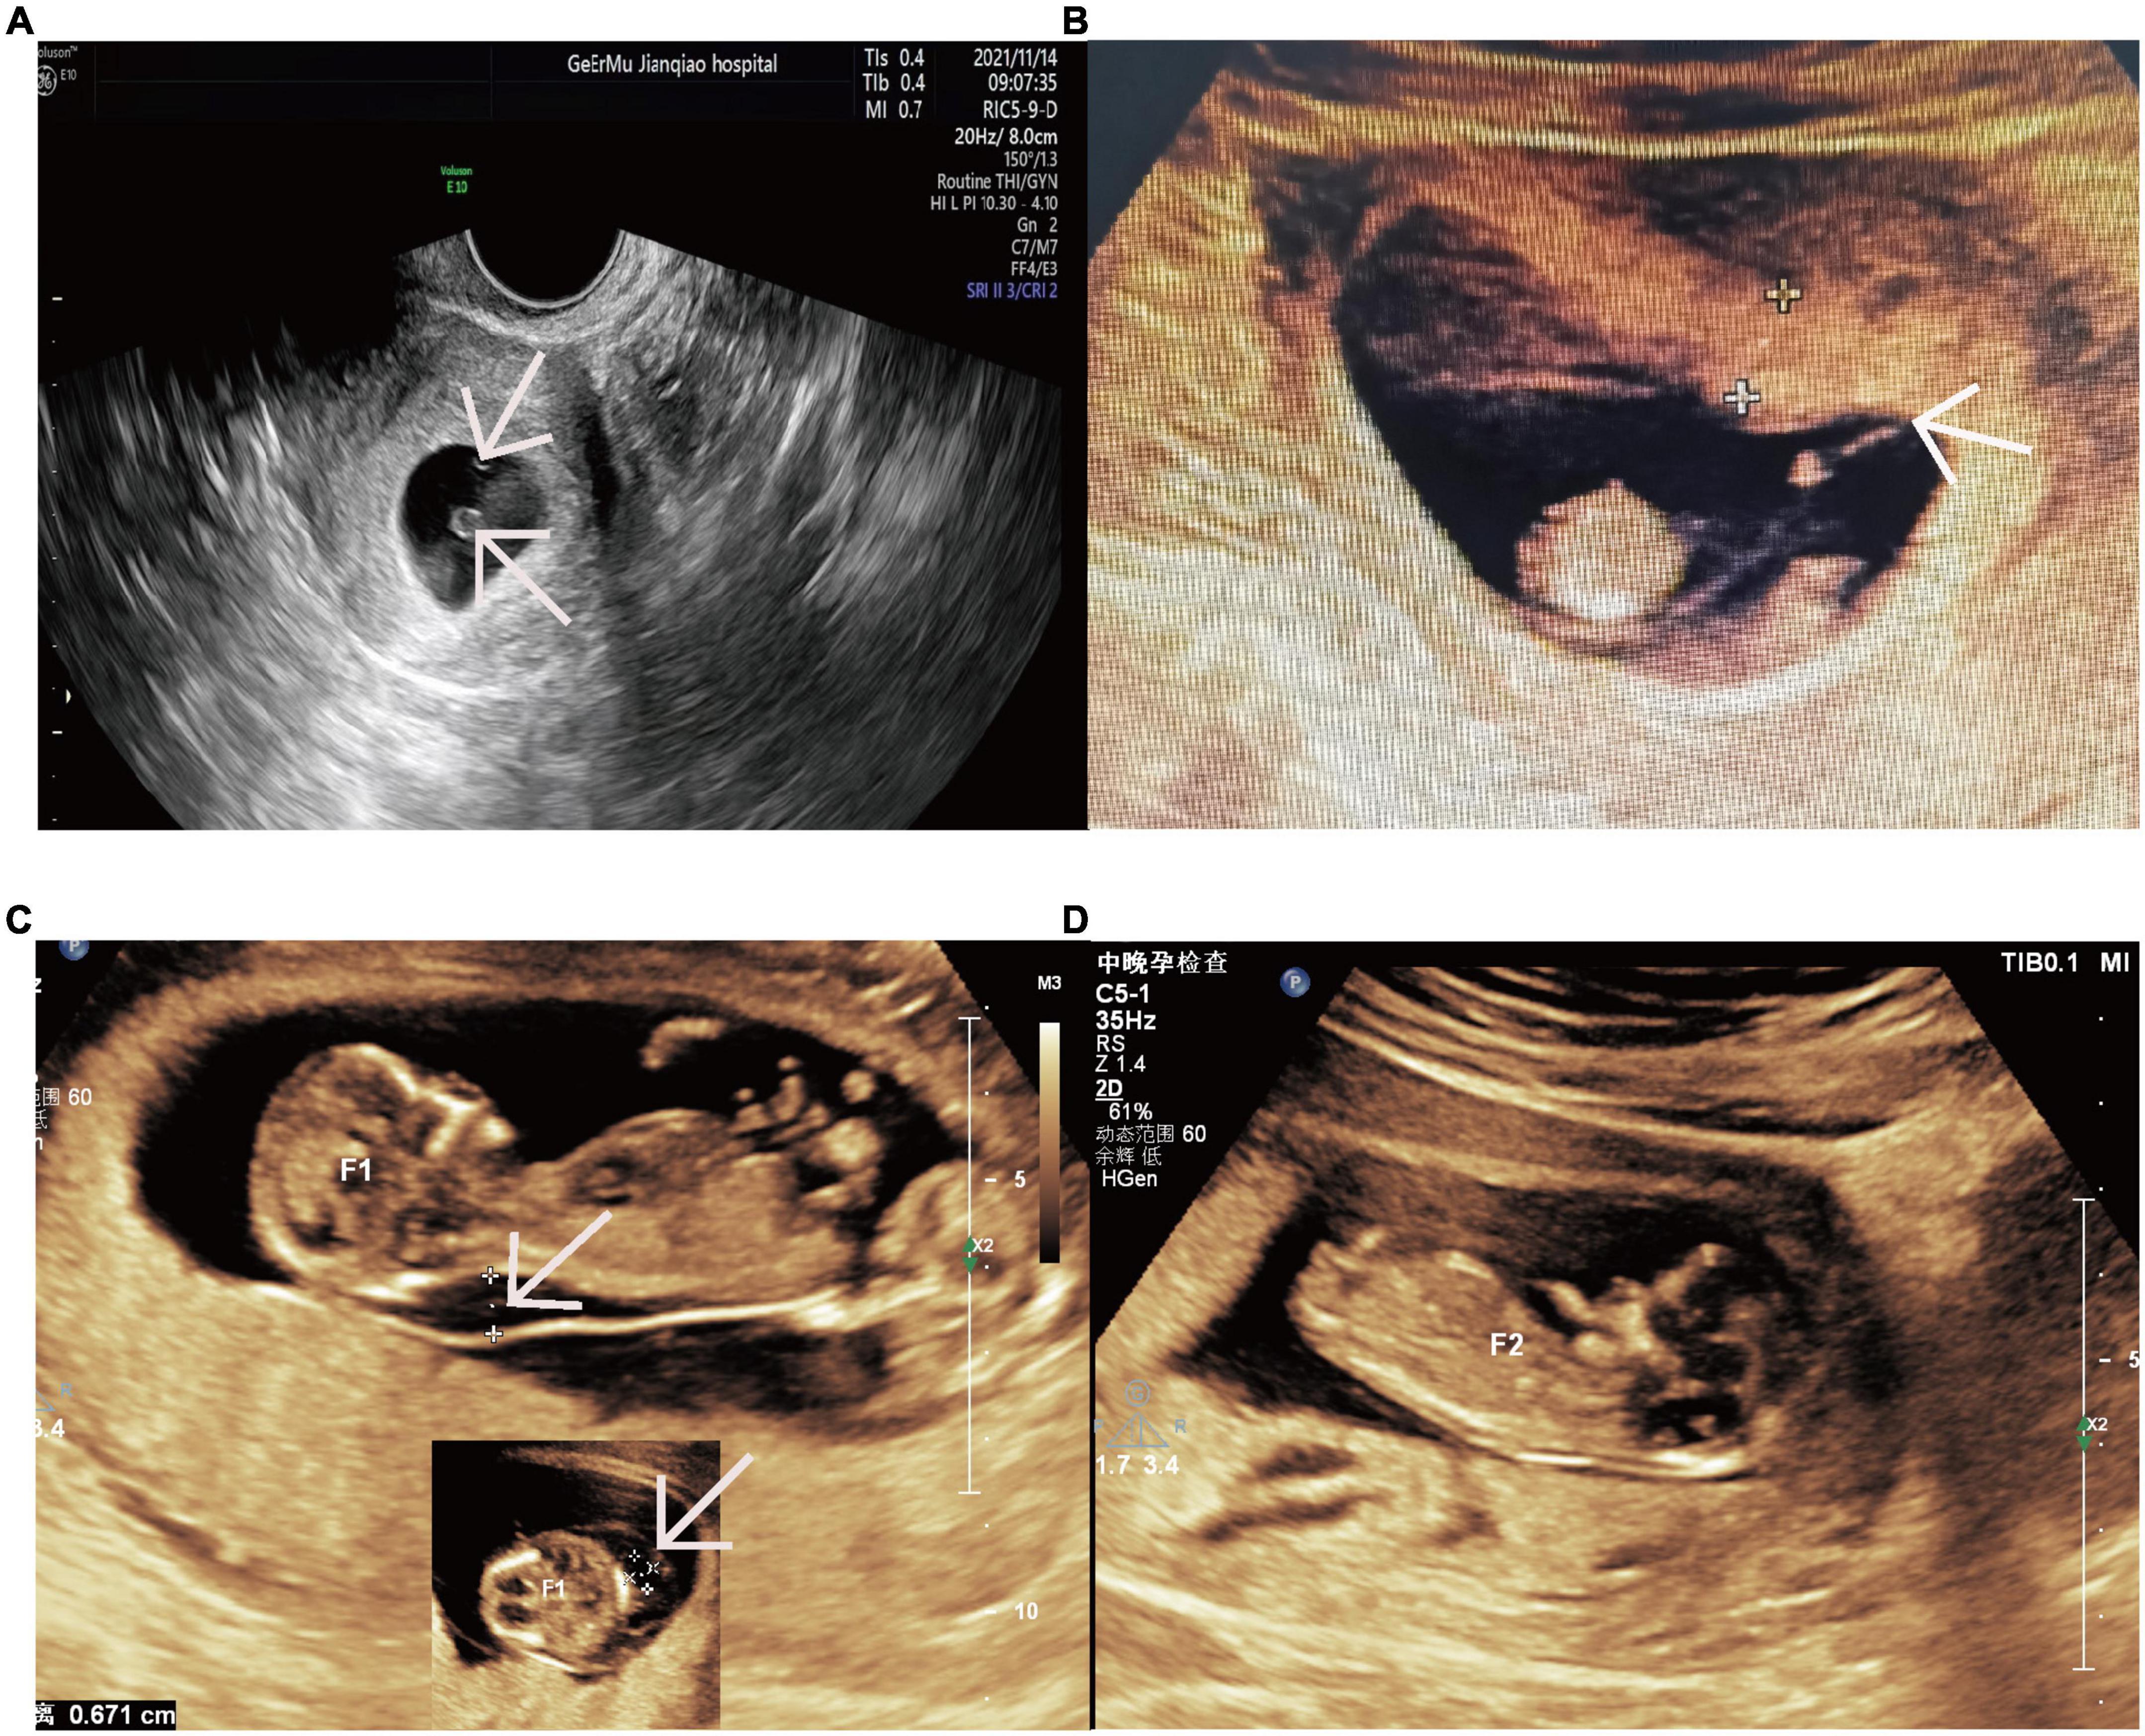

Optimize your heart health with advanced cardiac monitoring. Discover how modern wearable technology and clinical diagnostic tools track heart rate variability, detect arrhythmias, and provide real-time ECG analysis. Learn why continuous cardiovascular surveillance is essential for early disease prevention, improved patient outcomes, and effective management of chronic heart conditions through precise, data-driven medical insights.